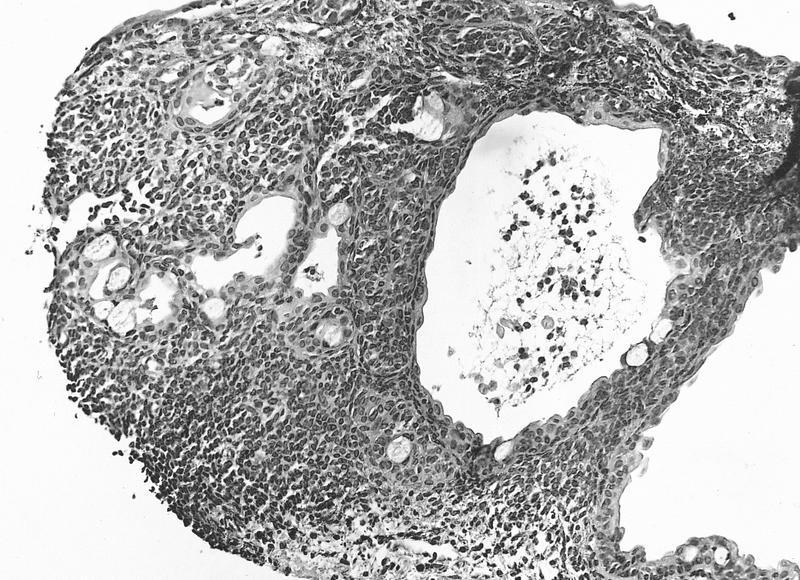

- Nevomelanocytes organized into intraepithelial nests of oval cells (type A), sheets of oval to cuboidal cells (type B), and spindled cells in subepithelium (type C)

- Often (50%) with solid and prominent cystic inclusions of conjunctival epithelium and chronic inflammatory infiltrate

- Compound (70 - 78%):

- Most common, nevi cells in epithelium and subepithelial connective tissue

- Cells have cysts lined by cuboidal and goblet cells and intranuclear inclusions

- May have large pigmented cells with prominent basophilic nucleoli

- Usually mixed inflammatory cells

Cystic compound nevus: